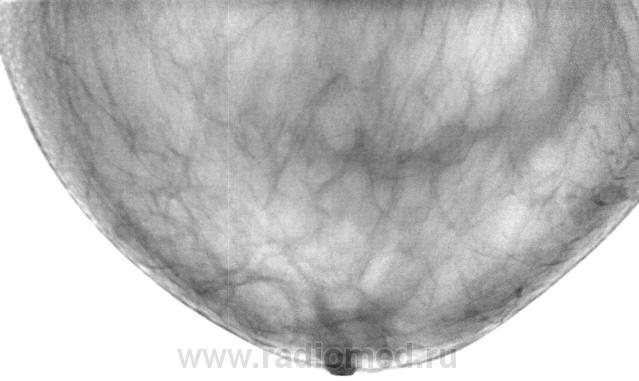

"Уплотнение" пропальпировано хирургом в передних отделах молочной железы...

На представленных снимках патологии нет, но учитывая наличие пальпируемого уплотнения нельзя исключить липому.

Да, действительно патологии не было, но хирург настаивал, и пациентку направили на консультацию к маммологу в ООД.

Правильно сделали,  в моей практике был один случай, когда уплотнение пальпировалось, размер до 2см, на маммограммах - полное замещение жировой тканью, в проекции пальпируемого уплотнения только "жир", на операции - рак, не помню гистологическую форму. Опытный онколог при пальпации отличит липому от более серьезной проблемы.

а практически по центру на всех маммограммах: разве не мелкий узел с тяжистым контуром, примерным размером 1.5-2 см (масштаб не ясен). такие вещи в ГО: аденокарцинома